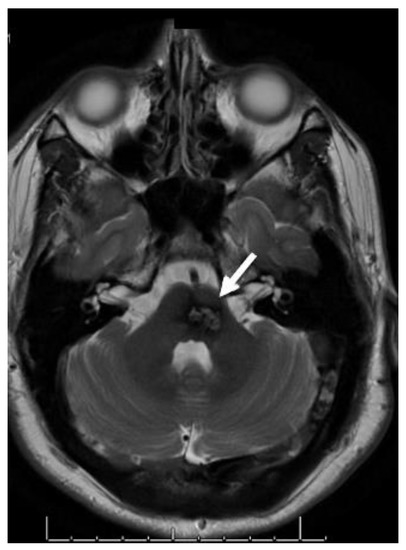

2. Epidemiology and Genetics of CCMs

3. Diagnosis